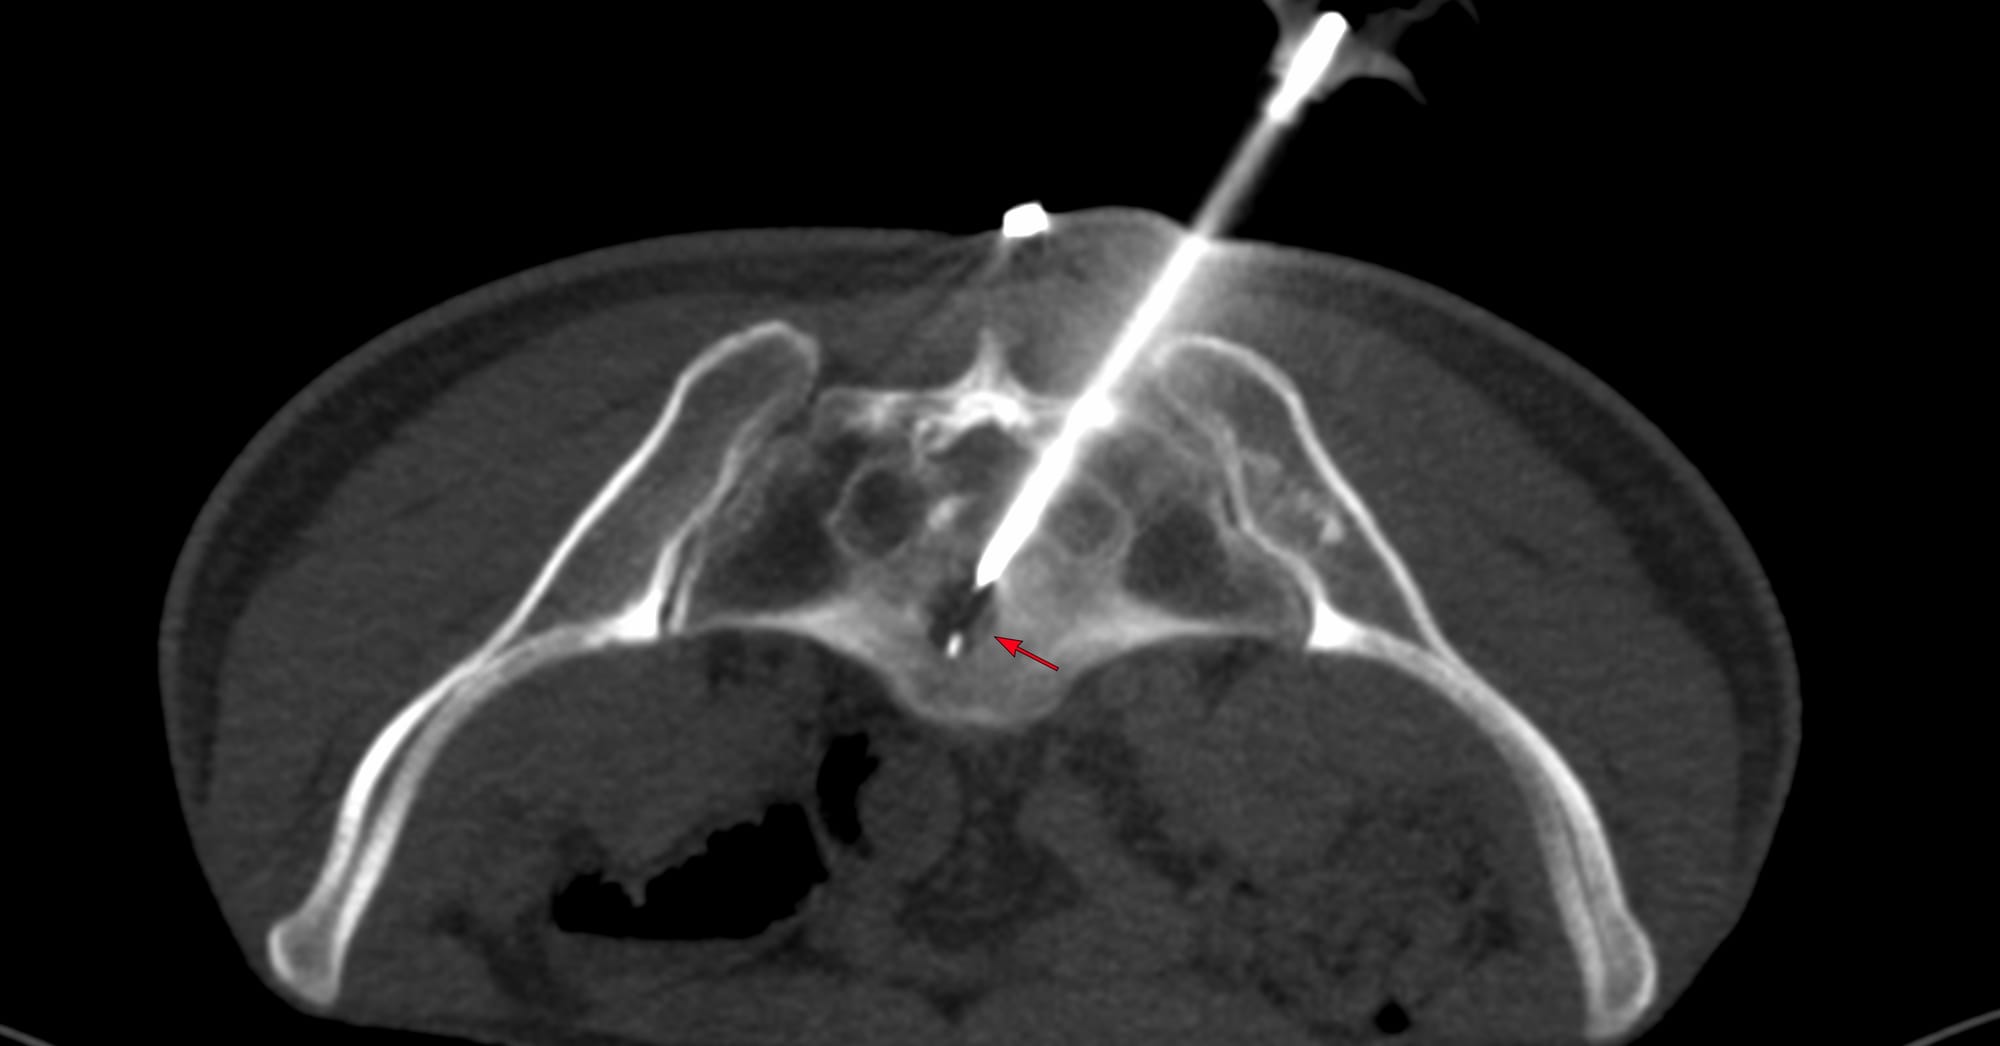

Case of the Day 100 - 2025 09 10 - T2 Dark Thoracic Spinal Vertebral Lesion - Transpedicular Biopsy

Bhavin Jankharia - 14 September 2025